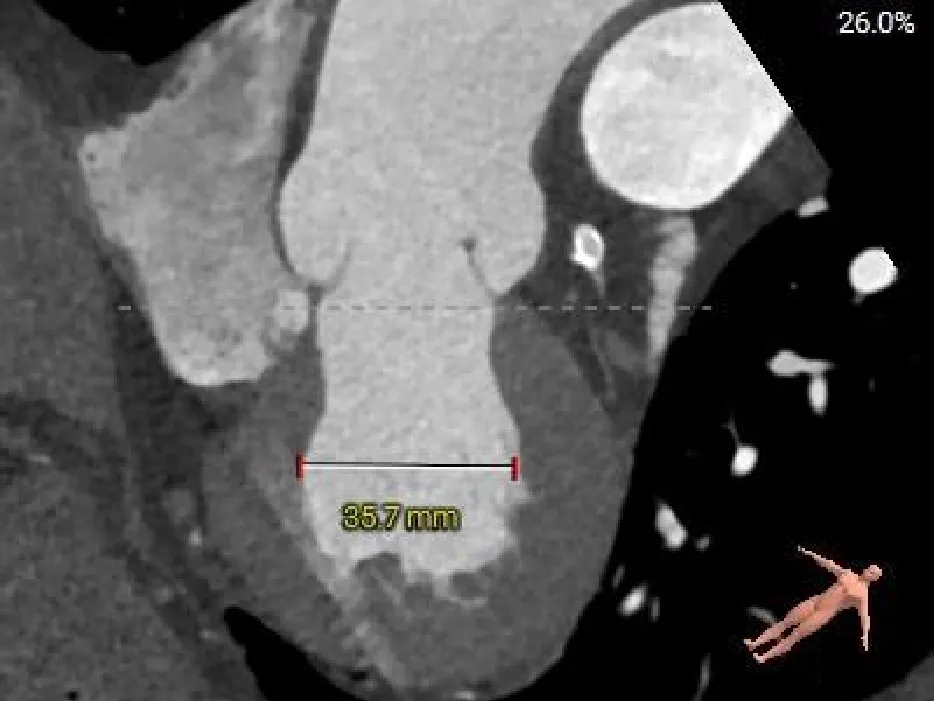

CASE Ⅰ

患者基本情况

基础信息:77岁,男性。

术前CT分析

主动脉根部测量

Annulus

26.6mm

LVOT

27mm

SOV

40.2*39.3*38mm

STJ

36.7mm

AAO

38.8mm

心脏角度

57°

纯反流三叶瓣,瓣环内径26.6mm

流出道偏直筒型

瓣叶轻微增厚、无钙化

57°,近似横位心